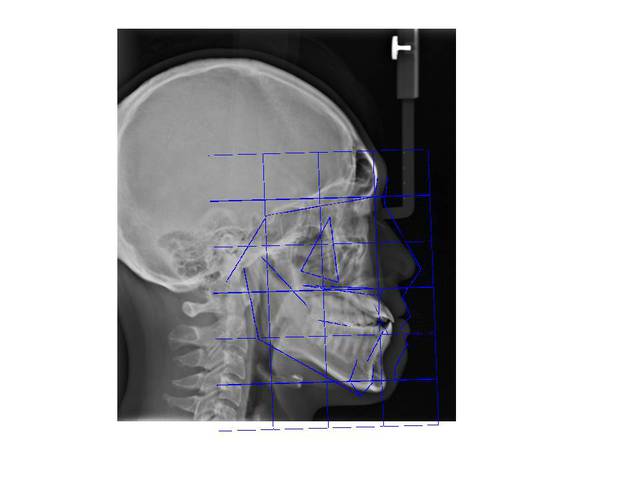

Patient asiatique, 25 ans, consulte car il veut corriger son crossbite bite antérieur localisé aux latérales et son crossbite secteur 2/3. Il aimerait également corriger son apparence générale, son profil notamment.

Classe III squelettique et dentaire.

Ci joints photos, ceph, modeles.

Le mesh utilisé ici est un asian mesh.

Par ailleurs ce n'est pas une prévision finale du traitement, c'est une aide au dignostic à base de normes préétablies de positionnement des points de repères.